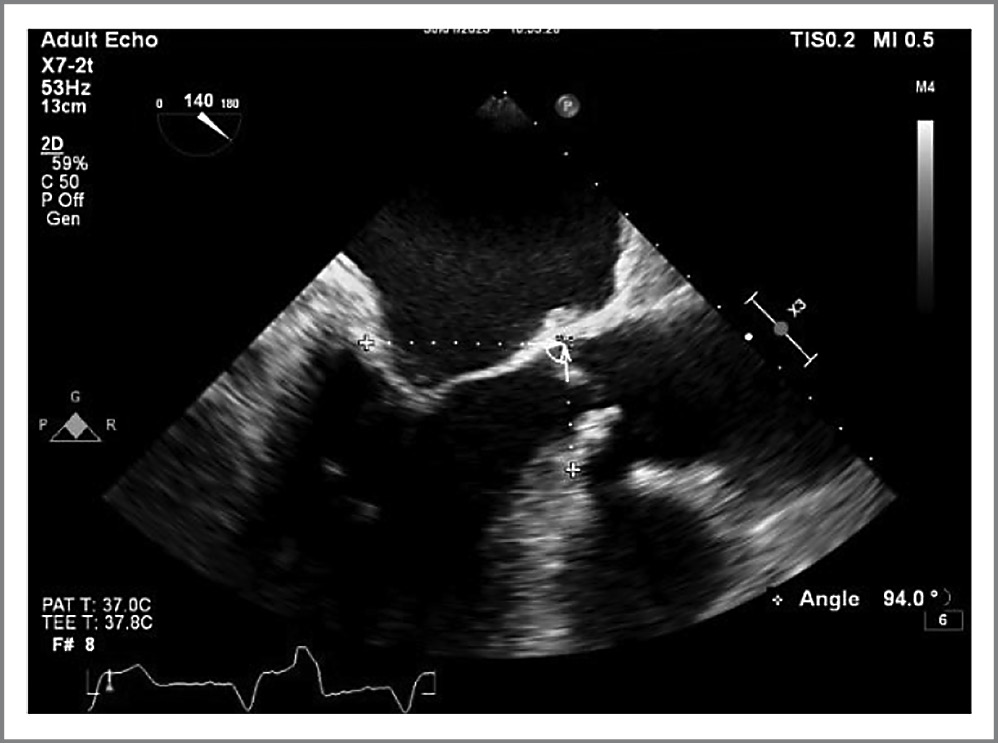

Учитывая абсолютные показания для коррекции аортального порока, у пациента с выраженной гипертрофией миокарда ЛЖ оценивались критерии риска развития SAM-феномена (передне-систолическое движение створок митрального клапана, в послеоперационном периоде приводящее к обструкции выносящего тракта ЛЖ). По данным чреспищеводной ЭхоКГ из 7 возможных критериев в данном случае наблюдался один – митрально-аортальный угол составил 94° (SAM-критерий менее 130°; рис. 9). Также оценивался риск возможной дислокации протеза в аорту на фоне устранения постнагрузки на ЛЖ и развития гиперкинеза гипертрофированного миокарда в послеоперационном периоде.

Рис. 9. SAM-критерий, митрально-аортальный угол <130° (расчетное значение 94°).

Fig. 9. SAM-criterion, aorto-mitral angle <130° (estimated value 94°).